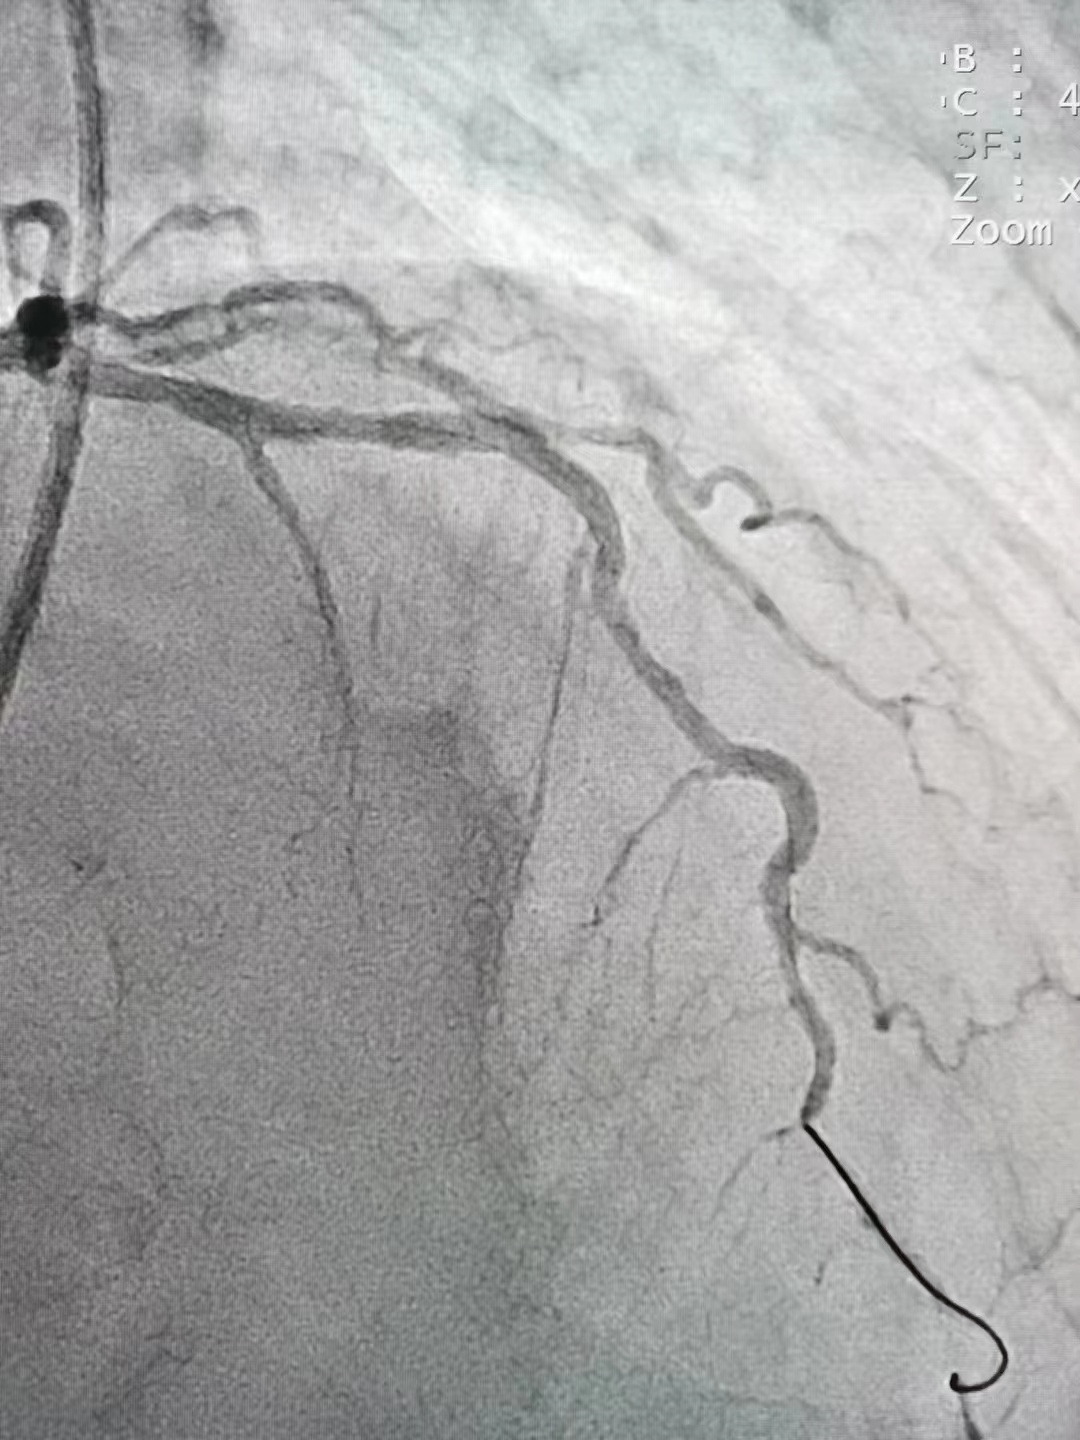

冠脉造影

冠脉造影结果:LM外膜钙化,内膜不光滑,中段狭窄90%,TIMI3级。LCX外膜钙化,内膜不光滑,TIMI3级。RCA外膜钙化,内膜不光滑,近段狭窄80%,中段狭窄90%,可见破损斑块,TIMI3级。

冠脉内介入治疗